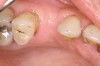

Figure 4  Clinical photograph showing preservation of the ridge seen in Figure 3.

Figure 4

To meet the needs of the new paradigm, treatment techniques have evolved for bone preservation. Figure 1 shows a case in which tooth No. 5 had advanced bone loss and the treatment option was to save it. The patient did not opt to have this treated, however. Figure 2 shows the same area approximately 18 months later when the advanced bone loss was also affecting the adjacent teeth. Traditional treatment—extraction of this tooth—would have led to a significant hard- and soft-tissue defect. Use of the alternative treatment—grafting of the socket at the time of extraction19,20—preserved the hard and soft tissue (Figure 3 and Figure 4). Grafting the socket to minimize postextraction ridge shrinkage is a much more conservative approach than performing ridge augmentation after extraction,21 which would have been required if the socket grafting had not been done in conjunction with the extraction.